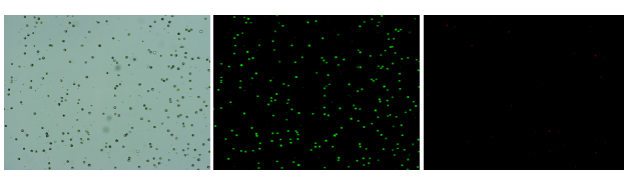

肝臟是人體代謝和解讀的器官,在體內(nèi)發(fā)揮氧化、儲(chǔ)存肝糖、合成分泌性蛋白合成等,肝臟也制造消化系統(tǒng)中之膽汁,人肝約有25億個(gè)肝細(xì)胞。但是解離肝臟組織懸液并不簡(jiǎn)單,首先,肝臟代謝旺盛,離體后肝細(xì)胞無法進(jìn)行正常的有氧糖酵解,細(xì)胞活力會(huì)迅速下降,另外,肝細(xì)胞的線粒體很多,每個(gè)細(xì)胞大約有1000個(gè)左右,遍布于胞質(zhì)內(nèi)。因此,很難得到符合單細(xì)胞測(cè)序要求的單細(xì)胞懸液。百邁客生物在肝臟組織單細(xì)胞懸液制備方面有豐度的實(shí)操經(jīng)驗(yàn),開發(fā)了獨(dú)有的解離體系,下面來看實(shí)驗(yàn)結(jié)果:

實(shí)驗(yàn)結(jié)果

人肝癌樣本,懸液背景干凈,活性91.69%,結(jié)團(tuán)率6%